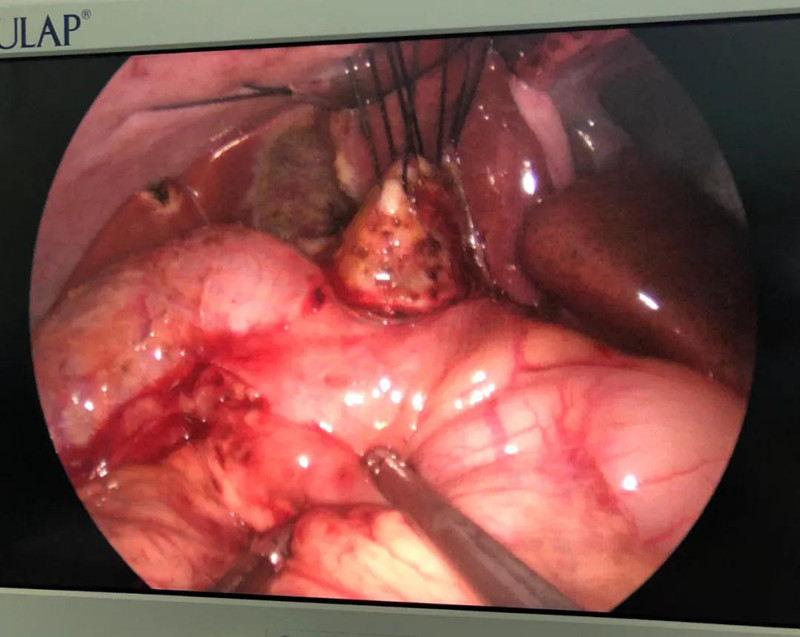

术前准备完毕。 9月25日,馨馨进入手术室。由崔钊主任带队,按照术前设计的方案,经过8个小时的奋战,手术成功了。馨馨肝总管以下病变的胆总管及胆囊全部切除,肝总管断面与肠管吻合接上,让胆汁直接流到肠腔里,帮助消化。如术后不出现胆瘘、肠瘘,没有梗阻,馨馨以后就可以正常生活了。目前馨馨恢复得很好,黄疸渐渐缓解,肝功正常,白细胞也降下来了,排气、排便都没问题,引尿管里也没有异常东西。

再谈及这台手术,崔钊主任说,其实当时手术的决定下得并不轻松,因为这台手术仅次于器官移植,相当于三、四项手术放一起来做。腹腔镜手术难度已经很大了,还是单孔,这也算是小儿普外科最尖端的微创手术了。

崔钊主任说,术前大家最担心的是门静脉出血,因为它比动脉出血更凶险,可危及生命。“馨馨来院时已经出现炎症,周围粘连严重。而静脉左侧临着肝总动脉,下边连着十二指肠乳头、胰腺,它和背侧的门静脉紧贴着,一不小心,就会导致门静脉出血。”

为了规避出血风险,术前,团队备足了血,又配备一名助手,一旦术中门静脉出血,马上开腹止血。另外,还有肝脏动脉变异的可能,幸好,术中这些个担心都没有出现。